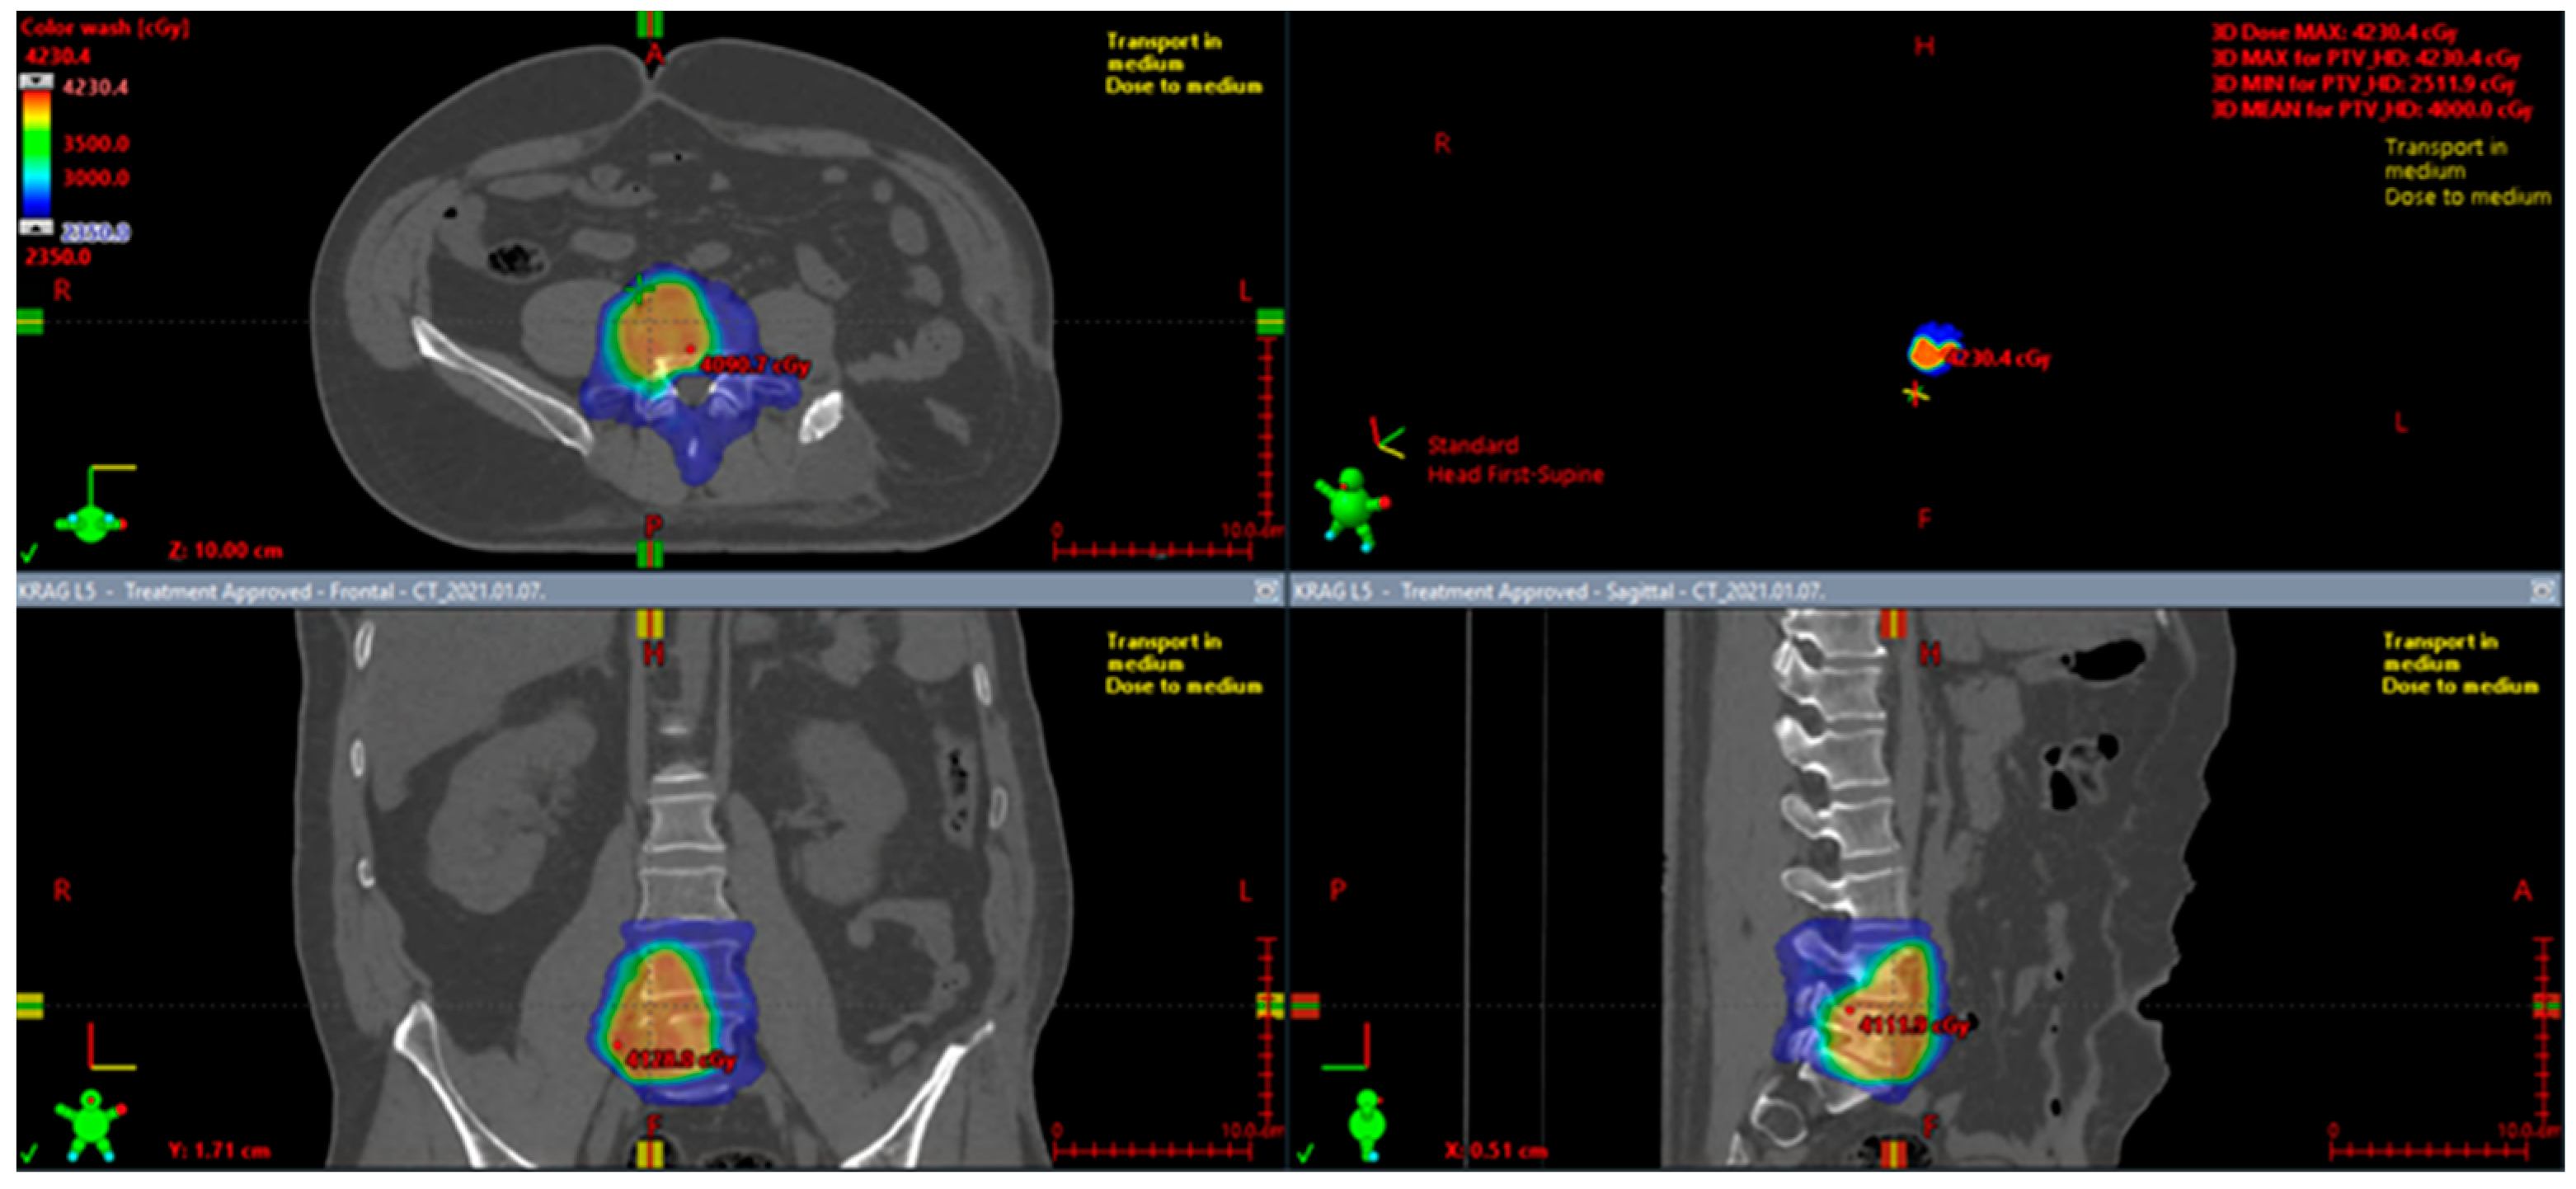

7.2. Perioperative Radiotherapy

7.4. Definitive Radiotherapy

- Spałek, M.J.; Teterycz, P.; Borkowska, A.; Poleszczuk, J.; Rutkowski, P. Stereotactic radiotherapy for soft tissue and bone sarcomas: Real-world evidence. Ther. Adv. Med. Oncol. 2022, 14, 17588359211070646. [Google Scholar] [CrossRef] [PubMed]